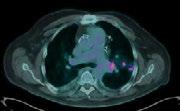

INTRODUCTION: Nuclear medicine imaging plays a pivotal role in evaluating complex prosthetic joint cases, particularly when conventional modalities are compromised by metal artifacts and nonspecific findings. This case study illustrates how the combined use of Gallium-67 scintigraphy and FDG PET imaging guided surgical intervention and evaluated disease progression with superior diagnostic sensitivity

CLINICAL PRESENTATION: A 61-year-old military veteran with a right total knee replacement presented with several months of knee swelling and severe pain. Initial evaluations including CT, bone scan, XR, ultrasound with fluid aspiration and MRI were inconclusive due to metallic artifacts and complex prosthetic fractures with adjacent oedema. The patient subsequently underwent Gallium-67 scintigraphy following an intravenous injection of 150 MBq Gallium-67 citrate, with imaging performed 48 hours later using a GE Discovery 670 system. The Gallium-67 scan demonstrated a significantly abnormal periprosthetic uptake, consistent with clinical concerns for infection. This result expediated surgical intervention and tissue biopsy of the affected area. The biopsy results revealed an extremely rare form of Diffuse Large B-cell Lymphoma involving the joint prosthesis. An FDG PET scan was then performed on a GE Omni PET system which revealed intense metabolic activity within the right knee and left knee, subcutaneous upper back activity and an FDG-avid right iliac fossa lymph node, suggesting systemic involvement. The patient underwent 6 cycles of R-CHOP and is awaiting further surgical intervention for the affected knee.

DISCUSSION: Prosthetic joint-associated lymphoma is an exceedingly rare phenomenon, with fewer than 20 cases documented in the global literature. The utility of 67Ga in lymphoma diagnosis is historically well demonstrated and this case underscores the complementary value of Gallium-67 scintigraphy and FDG PET imaging in complex prosthetic joint scenarios. While traditional imaging modalities were hampered by metal-induced artifacts and non-specific findings, nuclear medicine techniques facilitated the critical differentiation between infection and malignancy. This case also highlighted the importance of evaluating 67Ga-citrate imaging in complex clinical presentations with a comprehensive understanding of the mechanism of uptake in relevant pathologies The integrated imaging approach not only prompted surgical management but also informed systemic treatment planning, highlighting the evolving role of nuclear medicine in addressing challenging diagnostic dilemmas

Figure 1. 67Ga-citrate scan

Shimadzu Award